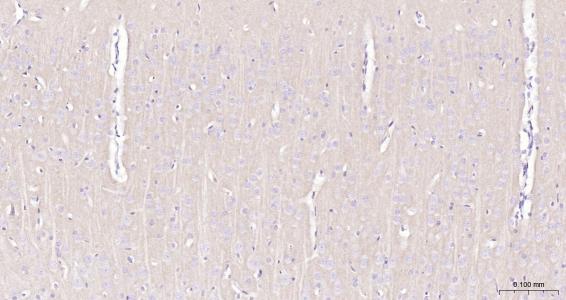

產品圖片

Paraformaldehyde-fixed, paraffin embedded Mouse brain; Antigen retrieval by boiling in sodium citrate buffer (pH6.0) for 15 min; Antibody incubation with GABBR2 Monoclonal Antibody, Unconjugated(bsm-54237R) at 1:200 overnight at 4°C, followed by conjugation to the SP Kit(Rabbit, SP-0023) and DAB (C-0010) staining.